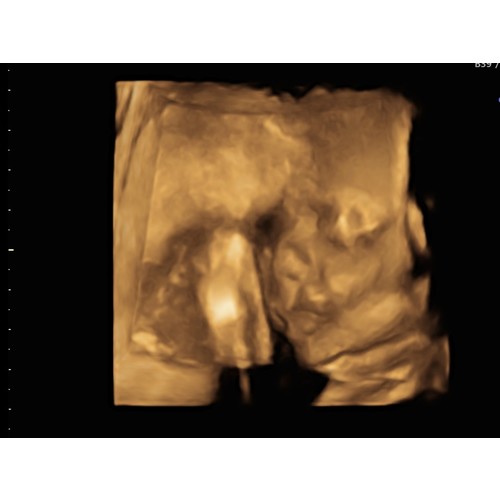

Staan ze er vanavond ook ? En wat kost het als ik vragen mag ? Wij hebben deze met 28 weken een 3D echo laten maken..zoooo speciaal. Bijna verslavend, dus zou het zo weer willen doen. Al denk ik dat het voor mij te laat is. 33weken, zal lastig worden om haar goed in beeld te krijge

Wij hadden met 15 weken een geslachtsbepaling en toen heeft ze ook een 3d filmpje gemaakt. Ik vond het net een kleine alien. Je krijgt geen goede indruk van hoe de baby eruit ziet 😔.

Ze zei toen ook dat je beter later een 3d echo kon laten maken.